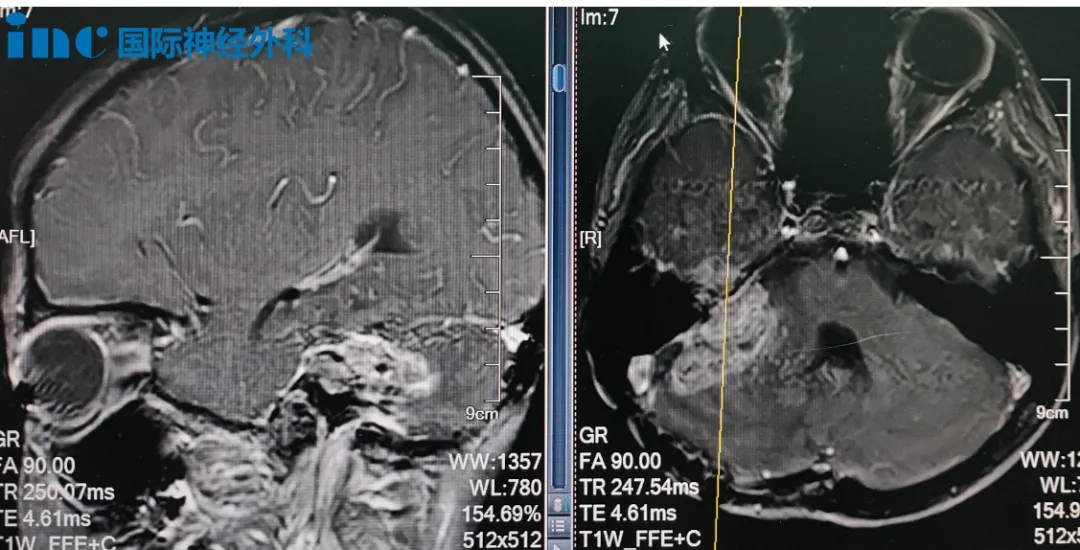

11岁的男孩小正,右侧桥小脑角区存在39mm x 27mm的巨大病变,他已历经2次手术、2次放疗以及化疗,如今找到巴教授,再次为希望而战。

(小正的术前MRI影像)